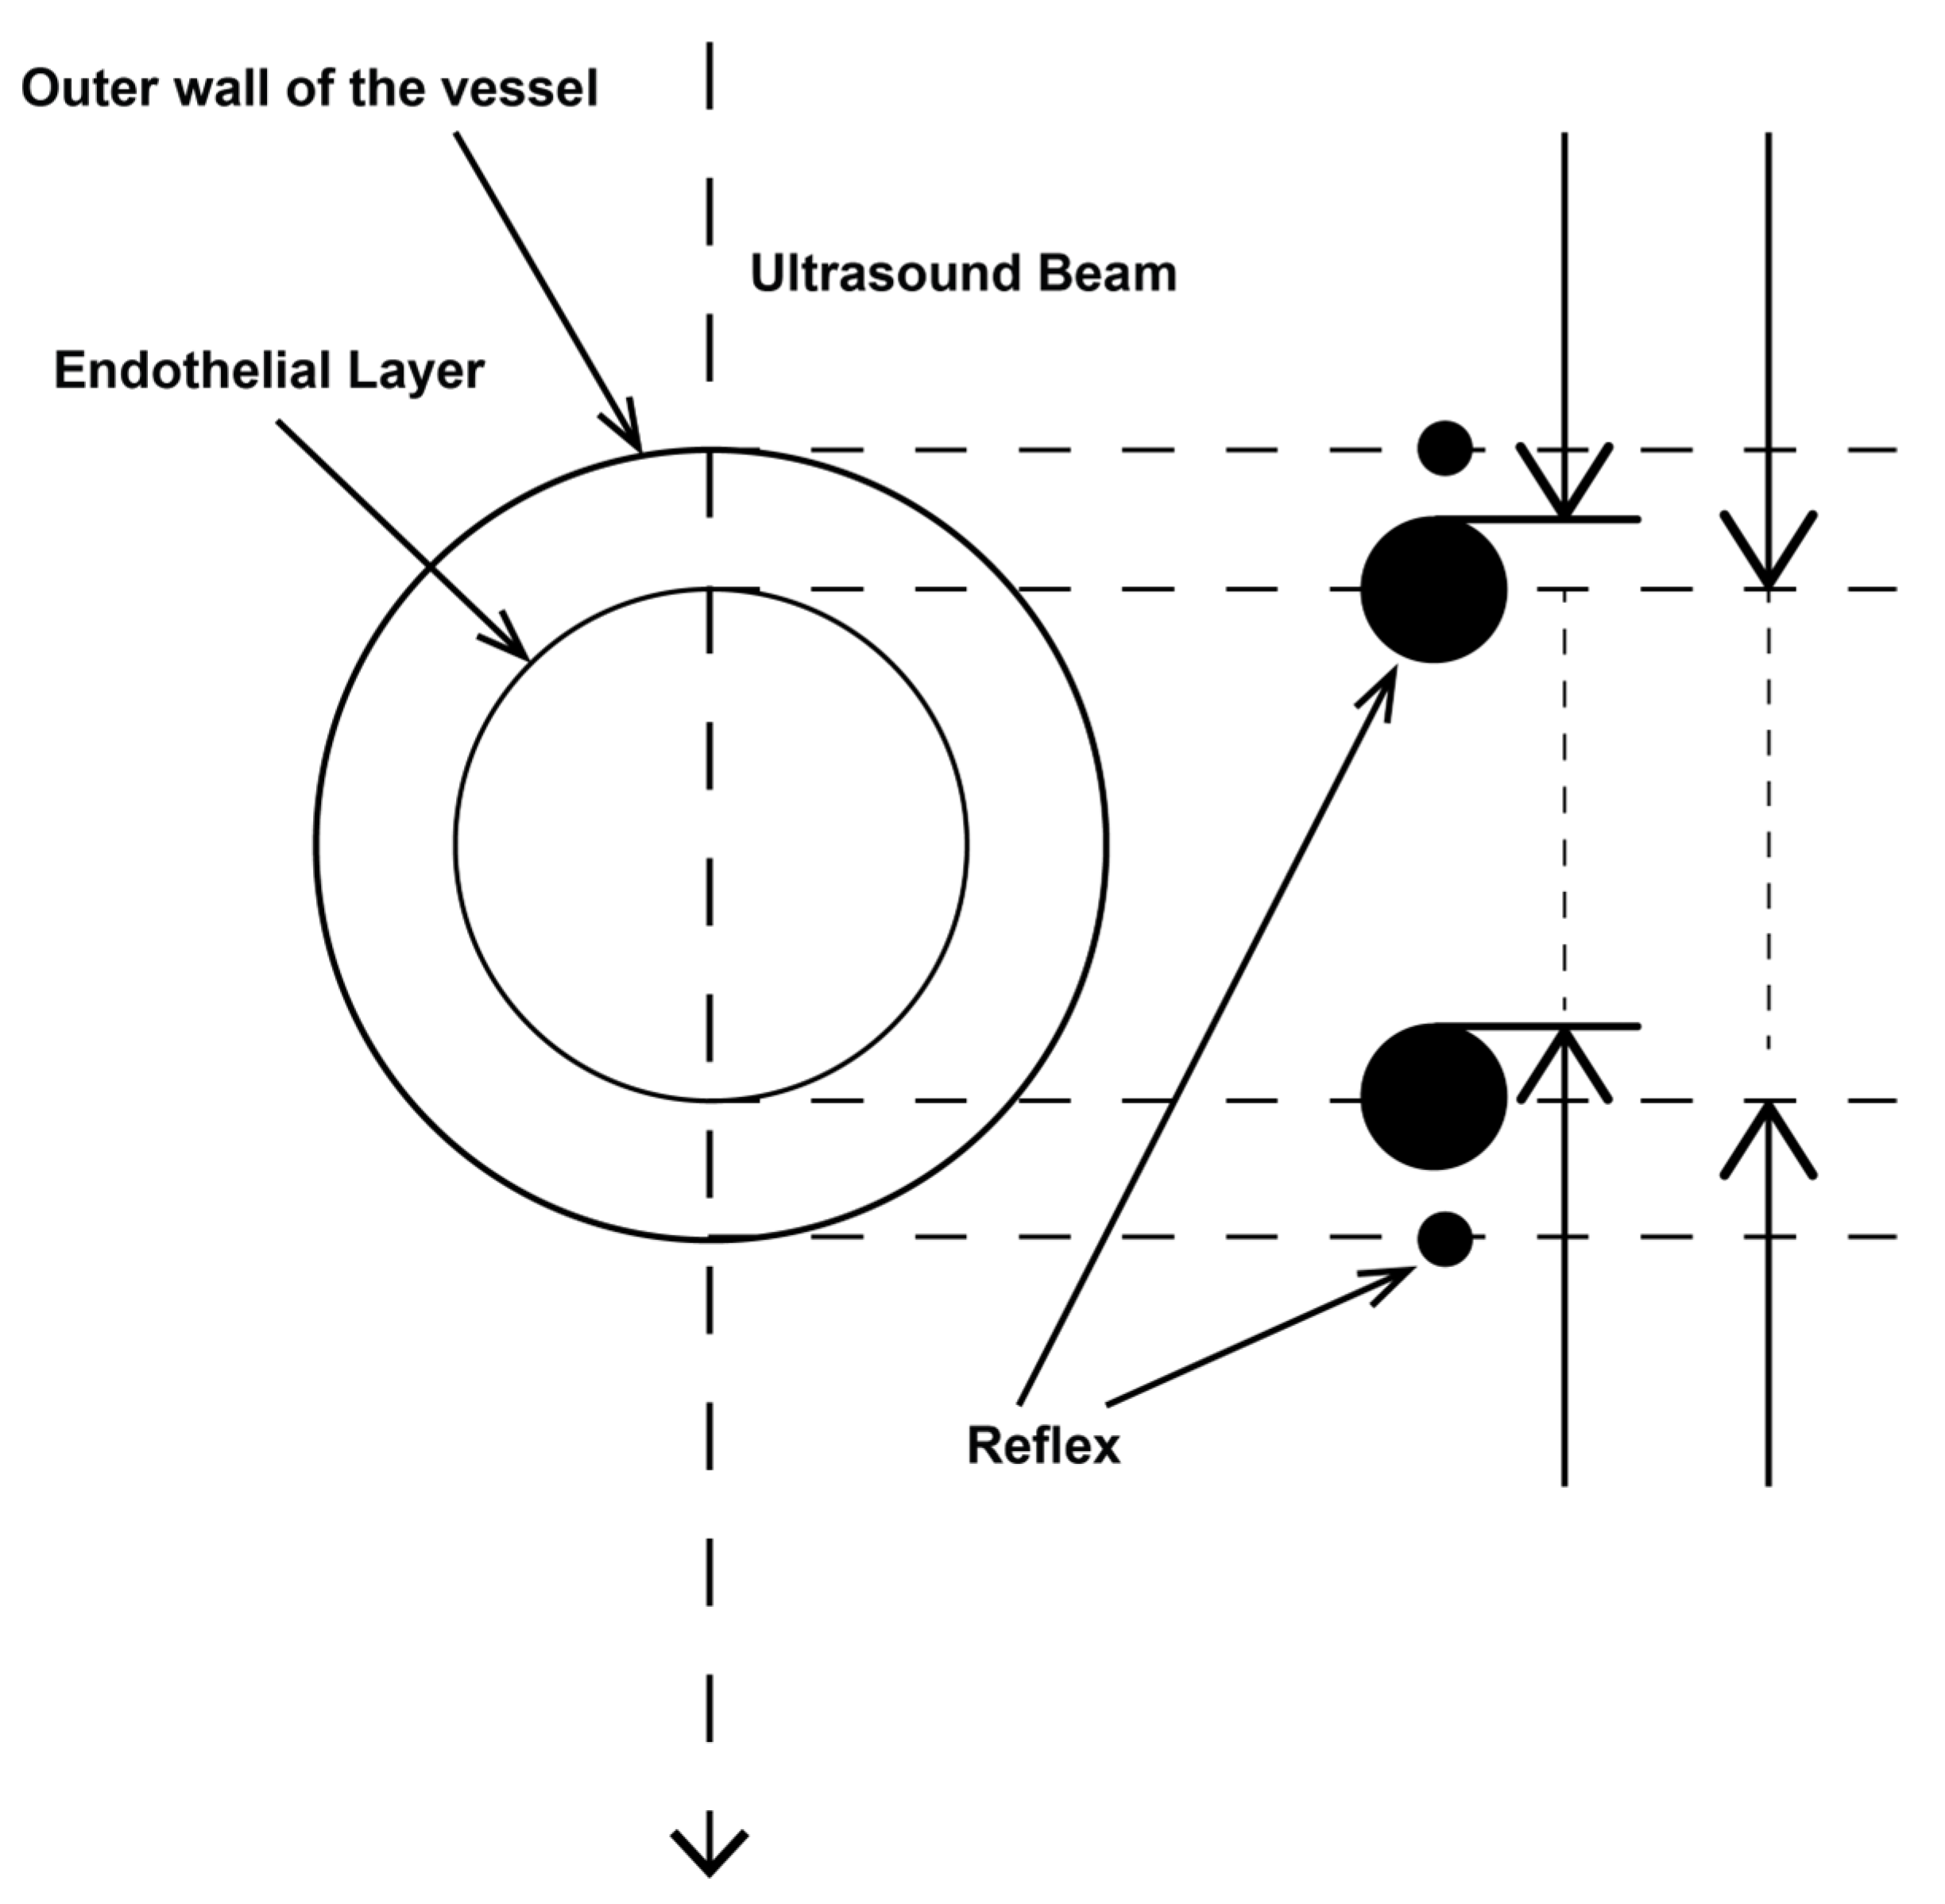

2.3.1. Determination of Vessel Diameter

2.3.2. Location of the Probe, Insonation Angle, and Doppler Window